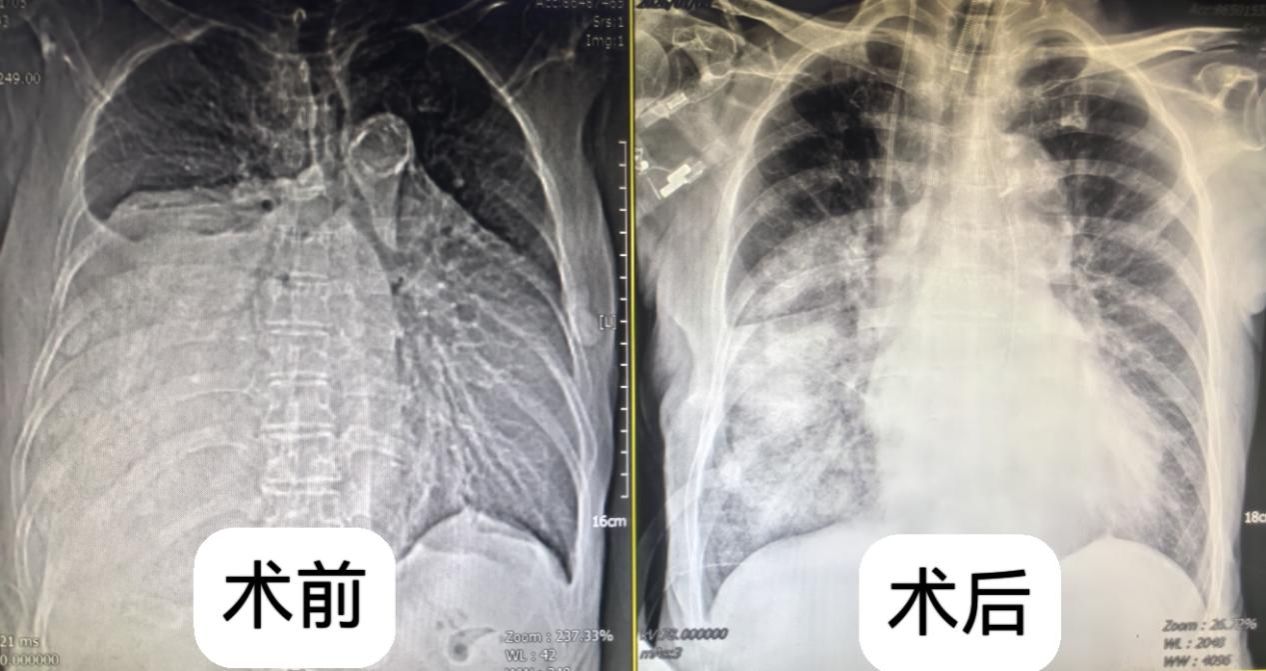

一年前,叶奶奶在体检中偶然发现纵隔占位性病变,当时肿瘤直径约 4 厘米,因无明显不适症状,且考虑到年龄较大,家属选择了保守观察。然而近半年来,患者逐渐出现活动后气喘、心慌等症状,近期更是发展到体力无法支撑正常行走,体重也随之下降。复查胸部 CT 显示,肿瘤已增至超过15厘米,占据右侧胸腔超过2/3空间,严重压迫心脏、大血管及食管,且与周围组织粘连致密,若不及时干预,随时可能因呼吸循环衰竭危及生命。

术中精细操作 + 术后科学康复 多学科全程护航